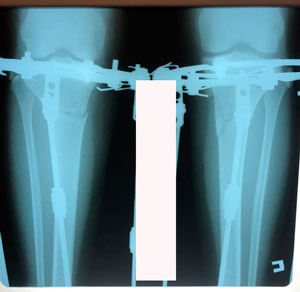

Исходник - 40 лет.

Дата операции - 09.06.2020

в процессе круток

на фиксации